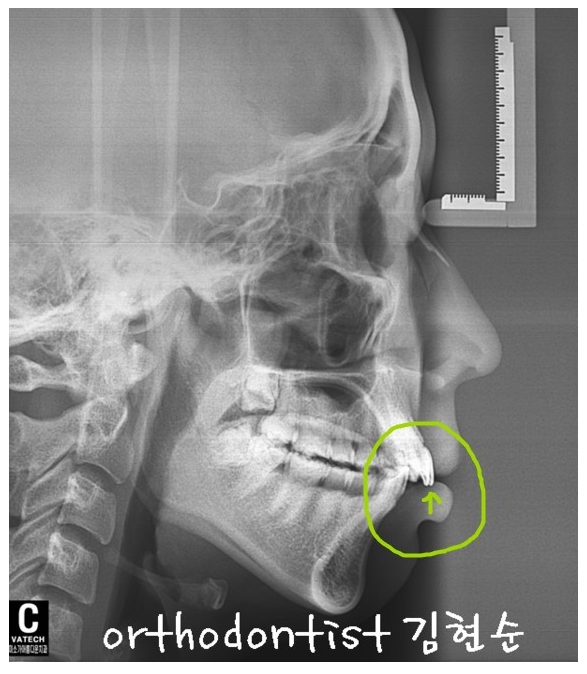

위의 사진은 세라믹 교정 진행하시기 전 정밀진단 X - REY 촬영 사진입니다 어떠세요? ..

사진의 보라색 동그라미 표시 화살표 보이시나요? ㅜㅜ

돌출된 앞니가 아래 입술을 밀어내니 아랫입술이 돌출되어 보입니다...ㅠㅠ

사진에 보이는 부분으로만 보면 아랫입술이 나왔구나 하고 보이고 X - REY 정밀 진단을 통해 심미선까지 고려한 정밀한 진단이 가능해짐으로 윗니 돌출로 인한 아랫입술이 나와 보이는 현상, 심미선까지 무너지고 또한, 무턱으로 보이는 모습까지 보이기도 합니다